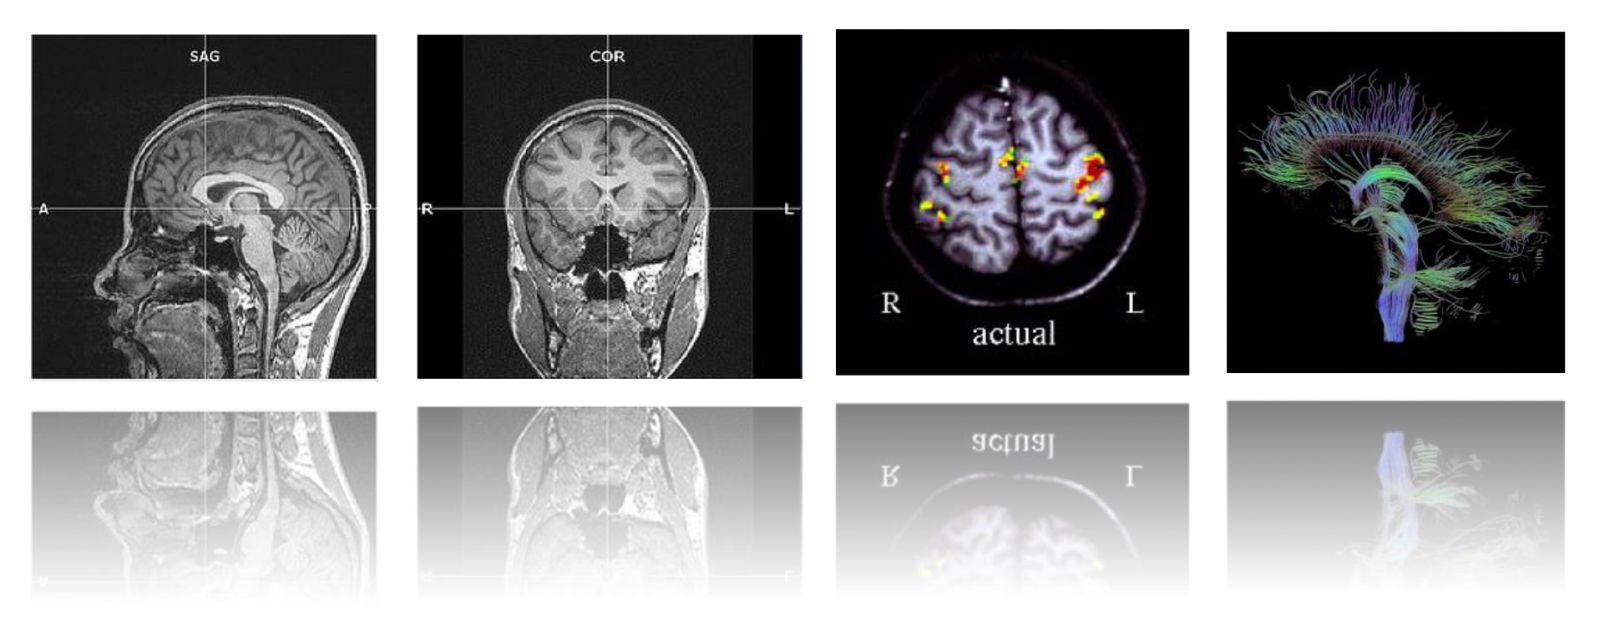

本次工作坊的主題是【影像醫學在精神醫學研究之理論與應用】,我們邀請到影像醫學的專家杜政昊博士 (Dr. CH Tu) 及陳君明博士 (Dr. CM Chen) ,深入淺出的帶領學員從理論到臨床實務、從操作到研究應用做系統性的授課。課程內容包括形態測量學(VBM)、皮質厚度分析(cortical thickness analysis)和擴散張量影像(DTI)等等。本課程特別優待台灣營養精神醫學研究學會之會員,年底前加入免入會年費!敬請把握!加入會員請點選:連結。

這是一個腦科學的研究世代,台灣營養精神醫學研究學會(TSNPR)致力於推動轉譯醫學 (translational medicine) 及跨領域 (interdisciplinary research) 的研究合作。本次工作坊的目的是希望透過系統性的介紹,讓有志從事腦科學研究工作的人員獲得紮實的影像醫學基礎知識,並透過講者的經驗分享,幫助學員掌握此領域的最新研究趨勢。